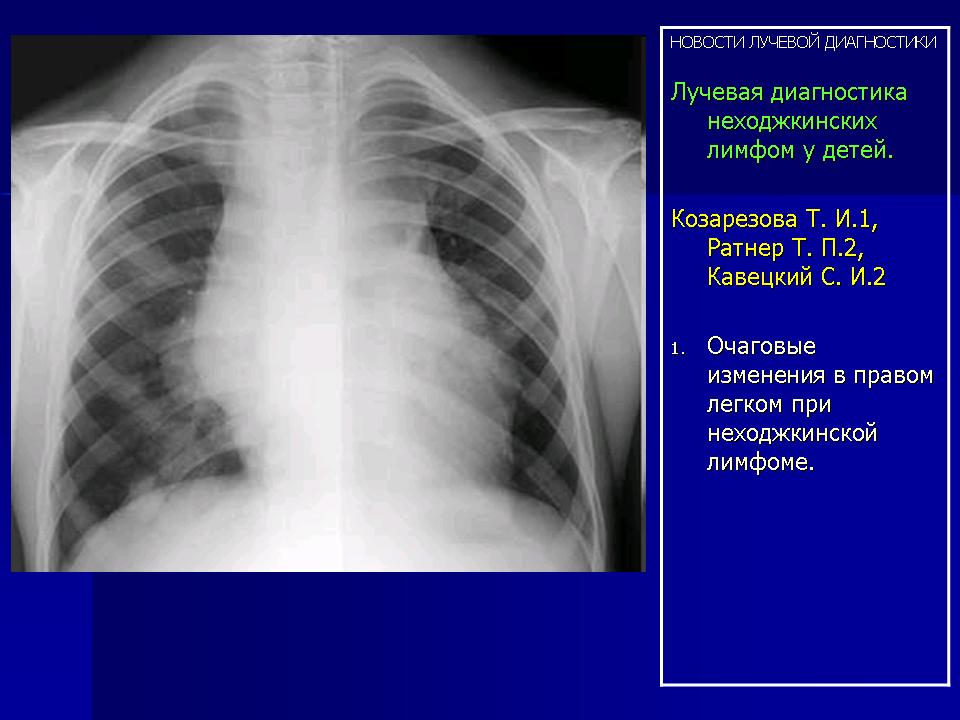

УЗИ лимфоузлов при лимфоме Ходжкина